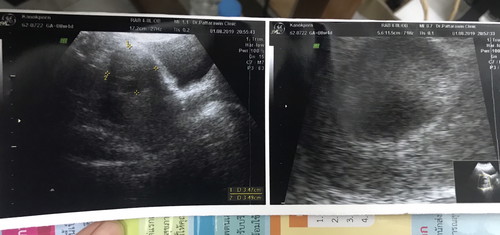

เมื่อวานไปฝากครรภ์มาคะ 7 week ยังไม่เห็นน้อง เห็นแต่การเต้นของหัวใจ แต่เจอเนื้องอก มีคุณแม่ท่านไหนเจอเนื้องอกบ้างคะ

เราเป็นซีสต์ค่ะ แต่คุณหมอบอกว่าไม่มีอะไรต้องกังวลเลยค่ะ เพราะฮอร์โมนคนท้องจะทำให้มันค่อยๆฝ่อไปเองค่ะ